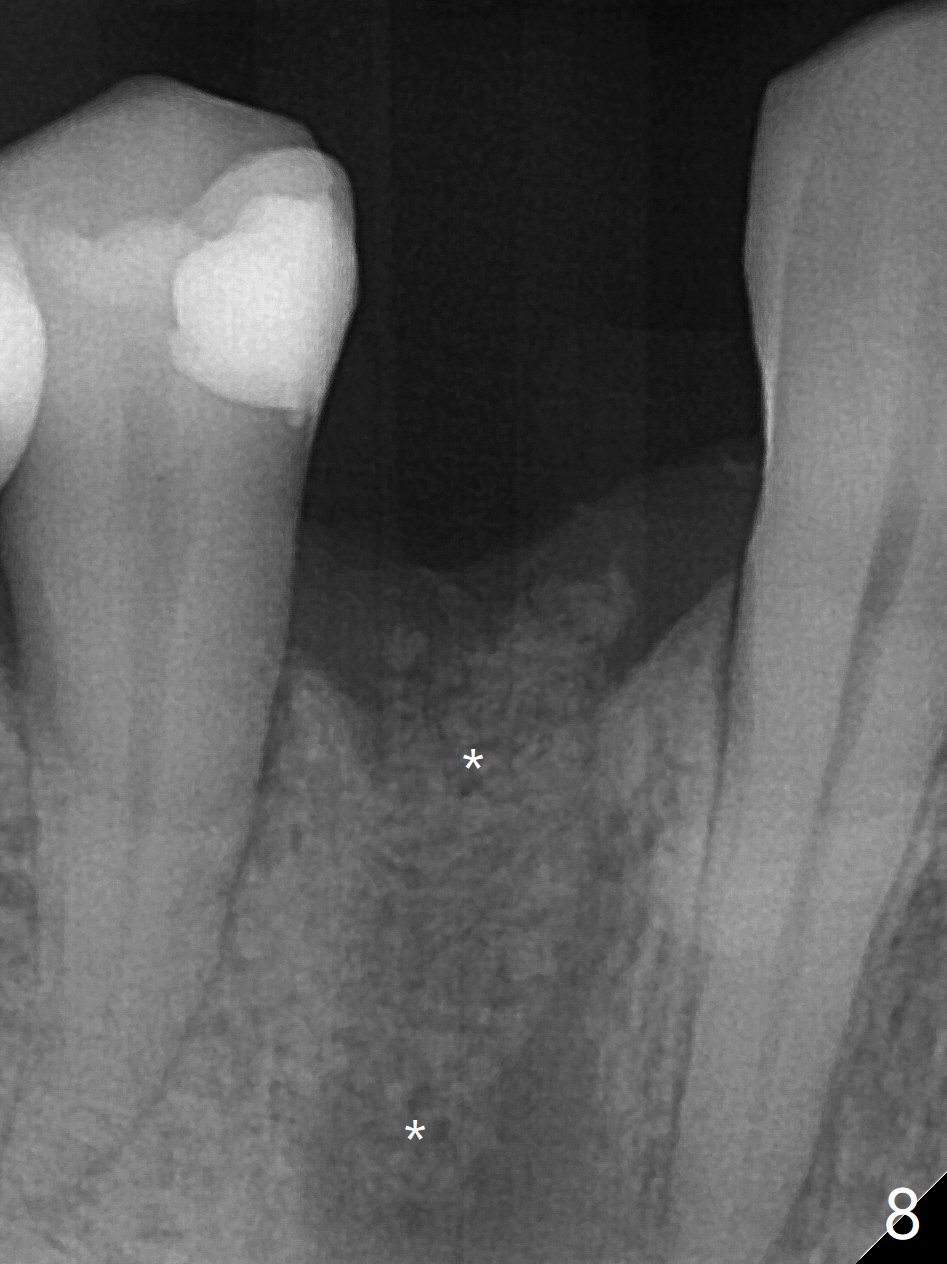

With 9 mm offset, the cylinder portion of the 2.2x8.5 mm drill does not engage to the metal sleeve of the guide at #28 after pointed drill (Fig.1). This issue could be solved with 12 mm offset, although it has no ill effect in this case. Fig.2 shows the site of #28 immediately before bone expansion and after use of 2.2x11.5 mm drill and small-scaled ridge split (^). The bone is so hard that the bone expansion is minimal (Fig.5) with autogenous bone graft and implant placement (Fig.4). There is the bone buccal to the implant clinically. A 5x10 mm implant is placed at #31 in the same appointment (Fig.3). Because of inability to masticate on the left (#18 root fracture with infection), the patient wants to restore #28 and 31 implants 3 months postop (Fig.6,7). The implant at #28 is removed while the healing abutment is being un-torqued without noting bone loss mesially (Fig.7 * (next similar case)). Bone graft is placed (Fig.8 (*),9). Pay attention radiolucency next the apex of the neighboring tooth (Fig.9 ?) before re-placement of an implant. The patient is upset, since he cannot eat. Two weeks later, a 6.5x4(4) mm cemented abutment is placed with 25 Ncm at #31 with a provisional for progressive loading for 2 weeks. Impression is taken. Two weeks later, a permanent crown is cemented without removing the underlying abutment. Two days later, the crown/abutment dislodges; a 6.8x6 mm healing abutment is placed. Eight days, it is difficult to reseat the existing crown and abutment. The mesiodistal edentulous space is limited as well. A 5.2x4(4) mm cemented abutment is able to be seated and torqued (30 Ncm) smoothly; in fact the clearance from the crestal bone (Fig.10 *) is not ample. If the abutment screw becomes loose in function, a profile drill should be used or a 4.5 mm in diameter abutment be placed. The abutment seems to remain in place immediate post cementation (Fig.11). Implant failure is probably due to no socket preservation (buccal plate atrophy) and too early restoration.